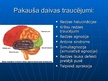

Smadzeņu pakauša, deniņu, paura un pieres daļas bojājumu neiropsiholoģiskie s...